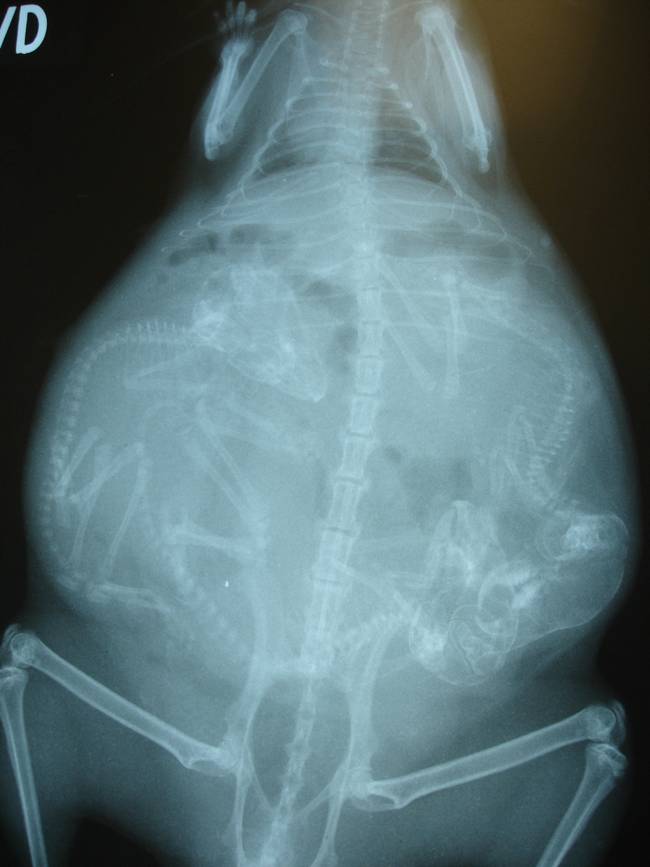

Gata